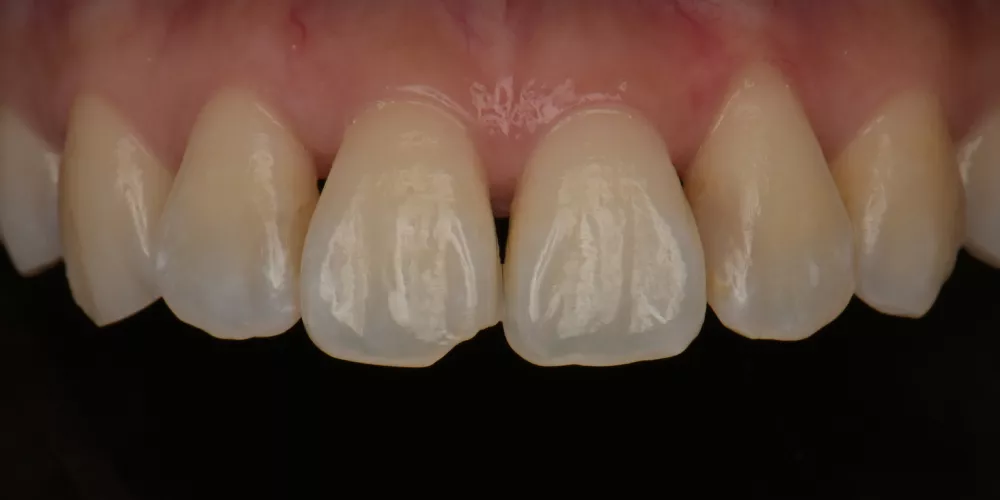

因此,每一次的治療,我都傾注最大的心力,在品質及細節上堅守高標準,讓成果真正經得起考驗。

身為職人牙醫師,我的責任不只是修復,更是透過專業經驗,為每一位患者把關未來。